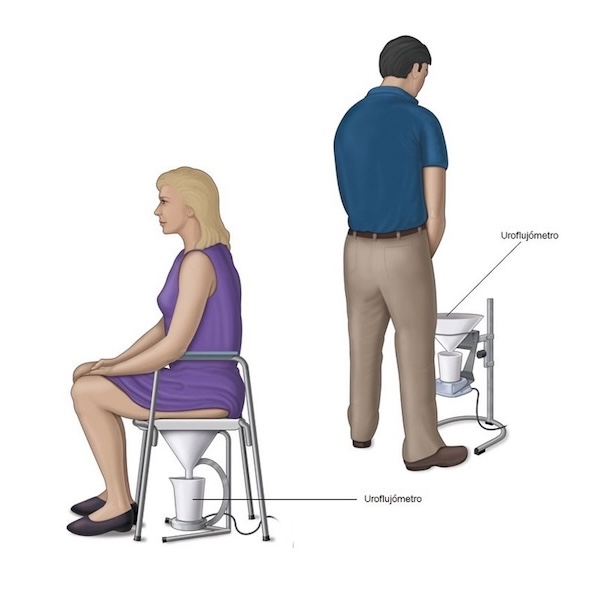

✔️ Chorro urinario fino o débil

✔️ Dificultad para iniciar la micción

El objetivo es eliminar la obstrucción y restablecer un flujo urinario adecuado.

⚠️ La evaluación especializada es clave para confirmar el diagnóstico y descartar otras causas de obstrucción urinaria.